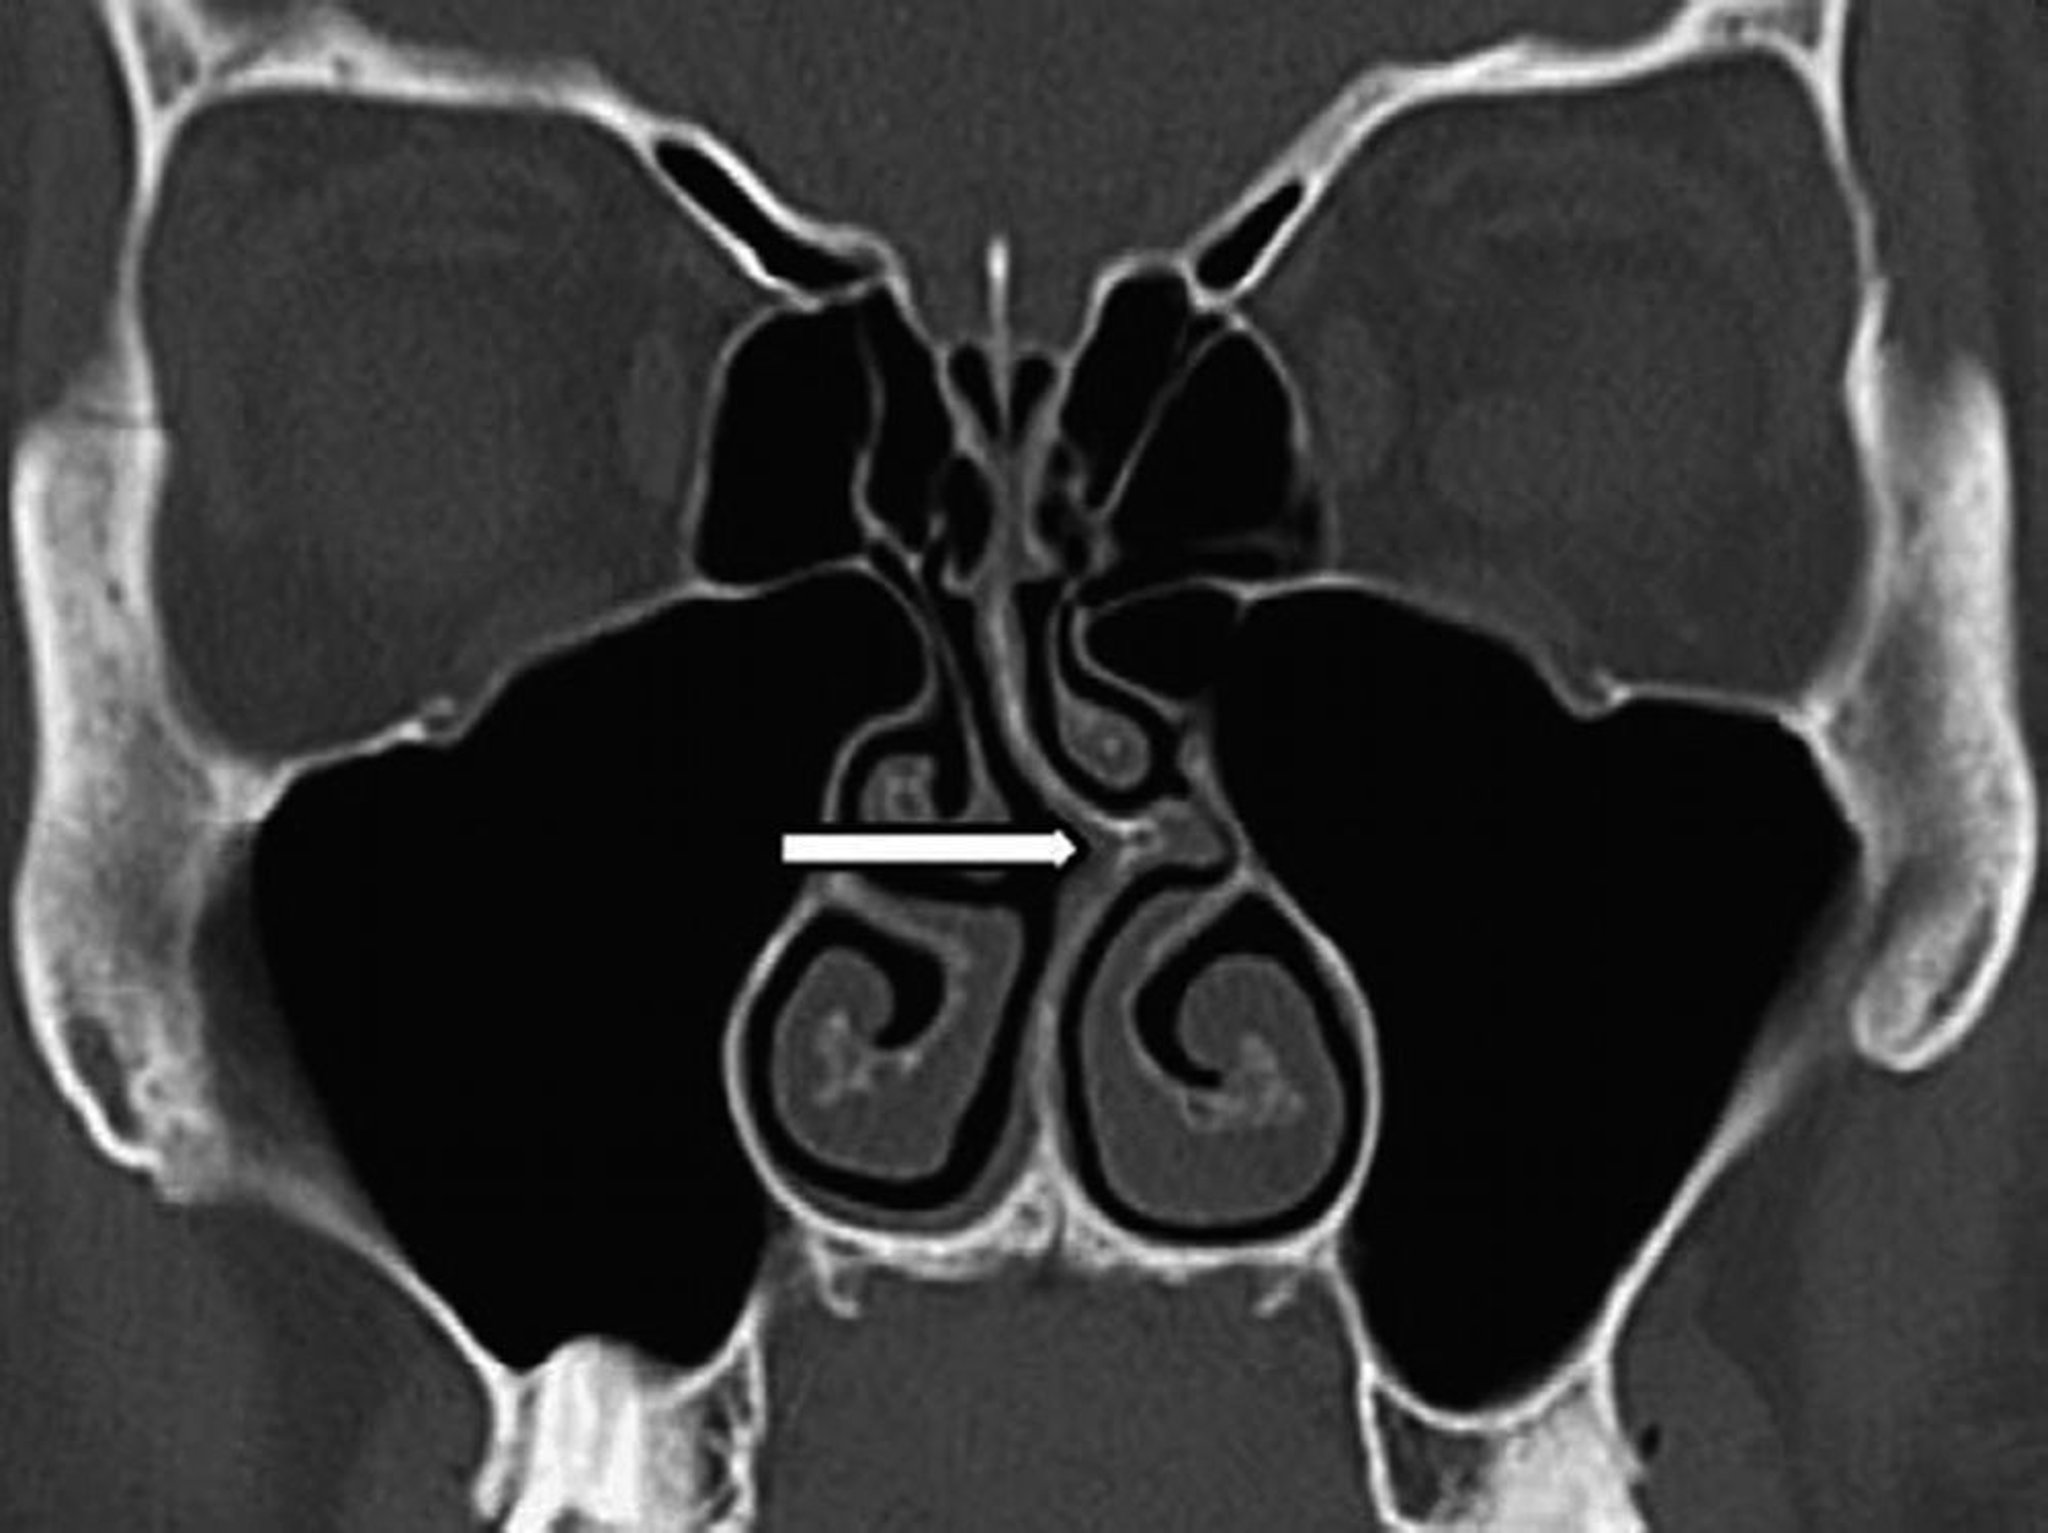

Déviation septale (TDM)

Cette TDM coronale montre une déviation de la cloison nasale vers la gauche (flèche).